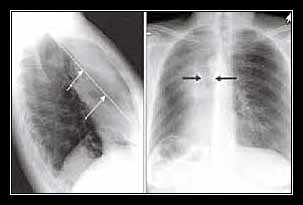

- Soi X-quang: nửa vòm nhô lên cao và bất động;

- Chụp X-quang: nửa vòm nhô lên cao.